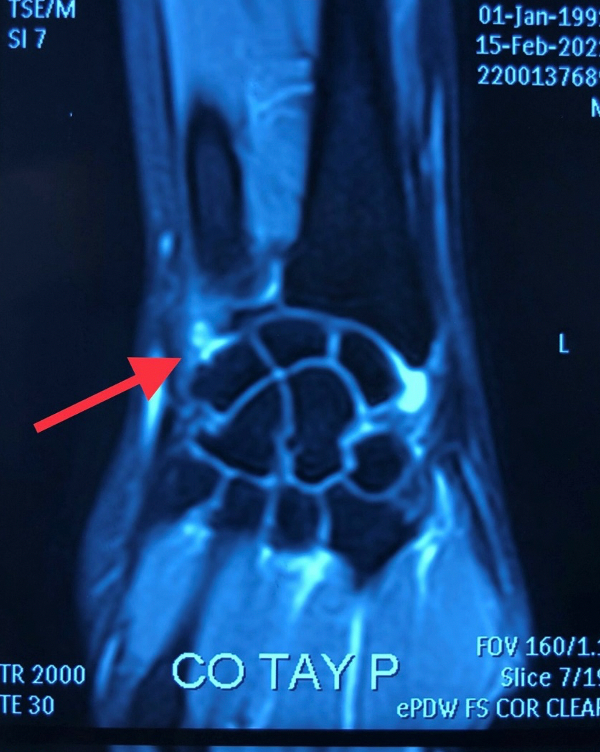

| Hình ảnh tổn thương phức hợp dây chằng sụn sợi tam giác TFCC trên phim MRI (Ảnh - BVCC) |

Đồng thời, cùng với việc chẩn đoán trên lâm sàng thì chẩn đoán hình ảnh cũng rất quan trọng, với phim Xquang thông thường khó phát hiện bệnh, cần dựa vào các kỹ thuật chẩn đoán hình ảnh chuyên sâu, ví dụ như phim chụp cắt lớp hoặc cộng hưởng từ.

Đặc biệt cộng hưởng từ có giá trị cao trong việc đánh giá, phát hiện cũng như định hướng các tổn thương, nhất là các tổn thương dây chằng ở cổ tay. Bác sĩ chuyên khoa chẩn đoán hình ảnh cũng phải được đào tạo bài bản mới có thể phát hiện được các tổn thương. Khớp cổ tay rất nhỏ, đòi hỏi các động tác tinh tế cũng như các trang thiết bị đặc thù, chuyên sâu như ống nội soi, camera, các dụng cụ kèm theo hỗ trợ.

Phim cộng hưởng từ cũng cho chẩn đoán tương tự như trên lâm sàng. Đây là một phức hợp dây chằng ở khớp cổ tay rất phức tạp. Ngày 2/3, Các bác sĩ đã quyết định phẫu thuật cho bệnh nhân bằng phương pháp nội soi tái tạo khớp cổ tay (điều trị tổn thương phức hợp dây chằng sụn sợi tam giác cổ tay- TFCC Triangular Fibrocartilage Complex).

PGS.TS.TTƯT. Nguyễn Mạnh Khánh - Phó Viện trưởng Viện Chấn thương chỉnh hình, Trưởng khoa Phẫu thuật Chi trên và Y học thể thao, Bệnh viện Hữu nghị Việt Đức - cho biết: Sau khi thăm khám các triệu chứng lâm sàng: đau vùng giữa cổ tay, mất vững khớp cổ tay phải, đặc biệt là vùng xương trụ, các bác sĩ đã nghĩ đến tổn thương phức hợp sụn sợi tam giác.